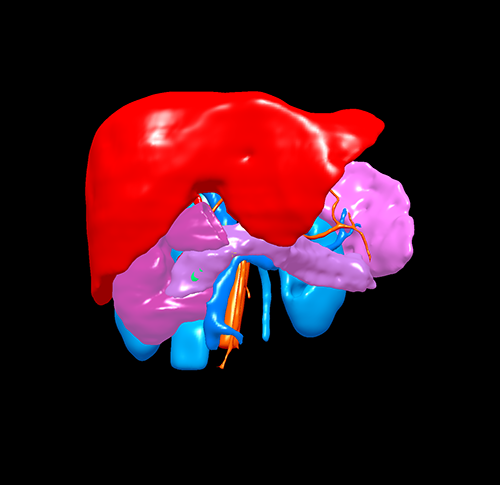

胰腺头颈假性乳头状瘤 -胰腺中段切除